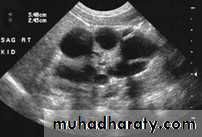

hydronephrosis